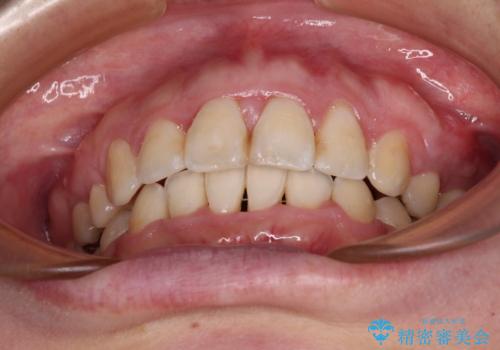

- 出っ歯と口の閉じにくさ、デコボコを気にして来院された患者様です。

口元の突出感を改善するため、上下左右第一小臼歯4本の抜歯を行い、ワイヤー装置による矯正治療を行うこととしました。

上下前歯の距離が大きかったため、上下の歯が接触するまでに時間がかかりました。

それでも目安である2年半で終えることができ、患者様には大変満足していただけました。